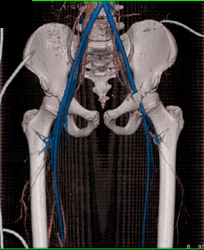

Diagnosis

Aortic Aneuryc With Editing Tool